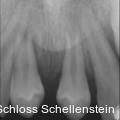

Gemination im Frontzahnbereich: Zahntransplantation als Therapieoption